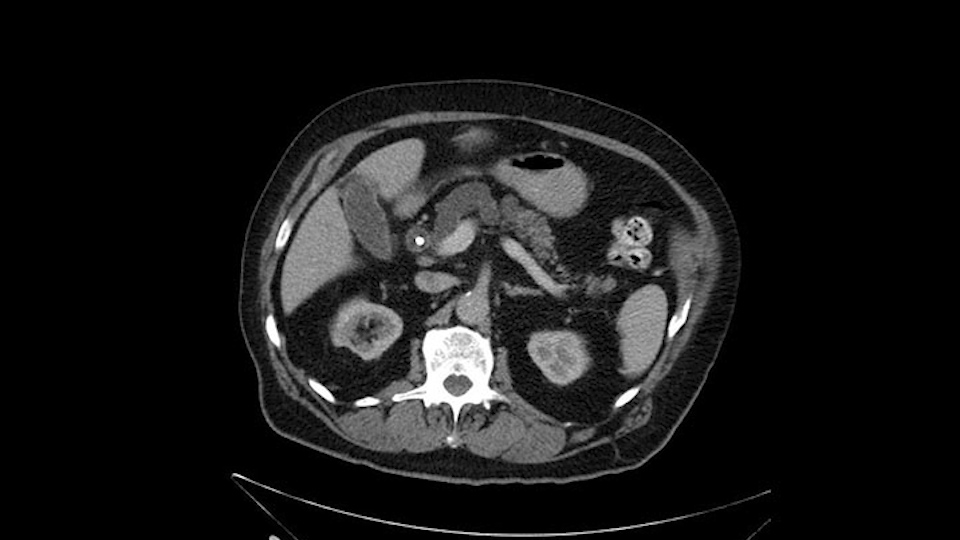

He has no liver metastases or obvious metastatic disease. On reviewing his CT scan, he has normal vascular anatomy; he has no involvement of the portal vein by the looks of it, or the superior mesenteric vein.

Anyhow. What the surgeon does need to do though, is focus on the resection. What I generally do is look at the tumor, which is here, and then I look at the nature of the pancreas. That’s really just to get an idea on what it would be like to do the pancreatic anastomosis, which isn’t technically the biggest deal, but it’s the biggest deal for the patient afterwards; and the larger the duct and the harder the pancreas, the less likely it’s going to leak. Leaks are what cause almost all the morbidity so I do think of it mentally. I wouldn’t do anything differently, the night before or the morning or the surgery or during the surgery, but certainly mentally it’s useful to know that you may have a challenge in terms of doing the best pancreatic anastomosis you can. I think the duct is quite large. The interesting thing about the duct: it does peter out into fairly normal looking pancreas; that’s a bit strange. But I’ll assume the duct is large.

Looking at the C.T. scan, the most important thing to determine is, of course, does the patient have any evidence of metastatic or disseminated disease or locally advanced disease? The imaging shows dilated intrahepatic biliary tree but I don't see any signs of liver metastasis. As would be expected with a ampullary lesion there's no evidence of major visceral vessel invasion. So this patient would look to me to be a candidate for pancreaticoduodenectomy or Whipple procedure.